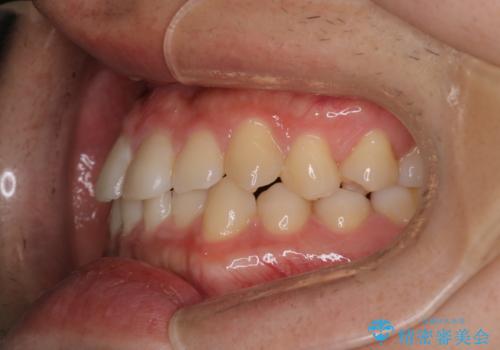

- 前歯のがたつきを主訴に来院されました。初診時、右上2番の口蓋側転位と右下7番の舌側傾斜が認められました。

インビザラインにてIPRと歯列弓拡大を行い、ゴム掛けで噛み合わせを改善する治療計画を立てました。

マウスピースの使用時間が短いため、シュミレーション通り進むか不安でしたが

治療期間1年で、主訴である前歯のがたつきを改善出来、

奥歯の噛み合わせも良くなりました。